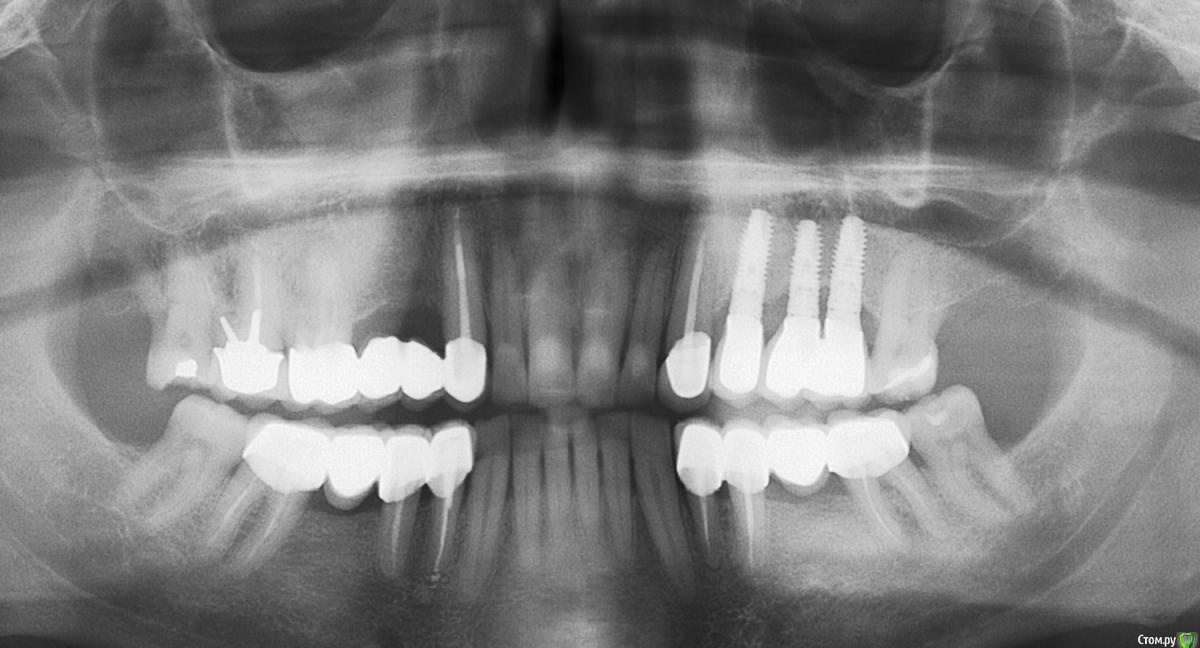

Анестезиолог Опубликовано 27 августа, 2017 Поделиться Опубликовано 27 августа, 2017 Пришло время менять мост на имплантаты (как видите, шестёрка справа сверху никуда, кажется это №16, есть симптоматика периодонтита уже неделю, еле-еле успокоил а/б и Нурофеном).Хирург посмотрел снимок и обратил внимание на стоящие уже. Прокомментировал следующим образом: "Надо было ставить не три импланта, а два, так как из-за того, что они стоят близко - средний и дистальный - нарушено питание костной ткани и она уходит. Кроме того, на названных имплантах слитные коронки, смысла в этом нет, только ухудшает гиг. мероприятия. Я поставлю два ипланта и мост на 3 единицы на них. Коронка на клыке останется временно, потом переставим".Вопросы:1. Правда ли, что есть ошибка в первой имплантации?2. Возможно ли не менять коронку на клыке? Жалоб писать ни на кого не собираюсь, судиться тоже, ответы не выйдут за рамки темы, просто мне для информации и планирования дальнейшей жизни части жевательного аппарата. Панорамные снимки моей улыбки в динамике прилагаю. Ссылка на комментарий

kriokov Опубликовано 27 августа, 2017 Поделиться Опубликовано 27 августа, 2017 только по пункту 1.близковато друг к другу имплантаты вкручены, кость соответственно уходит. Т.е переводя на русский, средний имплантат можно было не вкручивать. Убыль кости у Вас не от того, что не сделаны одиночные коронки на имплантатах. При адекватном расстоянии между имплантатами мосты с опорой на каждый имплантат хорошо работают, и долго. 5 Ссылка на комментарий

Kovalov Igor Опубликовано 29 августа, 2017 Поделиться Опубликовано 29 августа, 2017 по оптг искажение обычно сильное, сделать бы клкт и посмотреть какое расстояние от 23 до 27 зуба, от пики до пики костной. На мой взгляд тут проблема в ортопедии больше ... Отсутствуют же три зуба Ссылка на комментарий